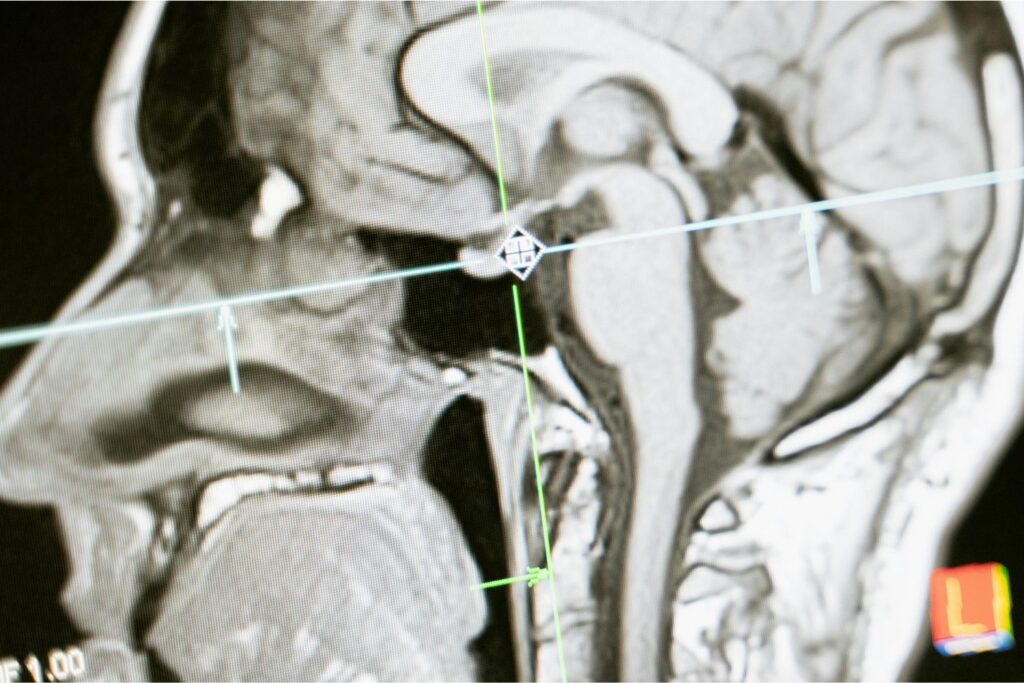

Un nuevo estudio comenzó a descifrar lo que ocurre en el cerebro de quienes trabajan jornadas maratónicas. Aunque se trata de una investigación inicial, sus hallazgos son tan sorprendentes como preocupantes. ¿Es posible que el trabajo excesivo esté alterando la estructura de nuestra mente sin que lo notemos?